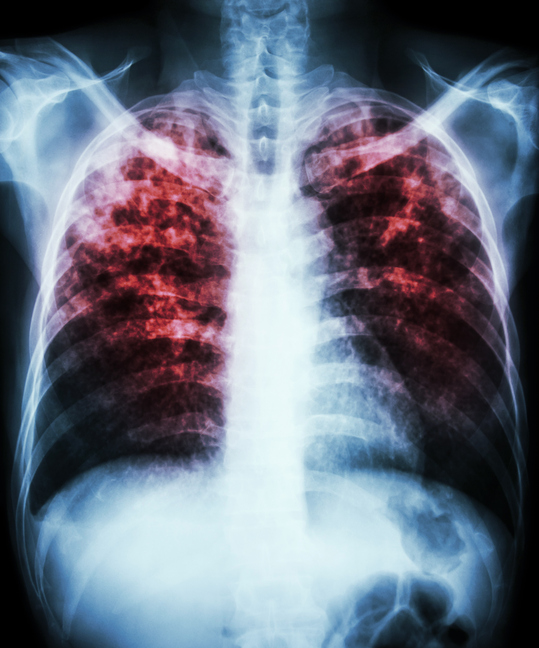

La bacteria de la tuberculosis suele atacar los pulmones, pero puede dañar otras partes del cuerpo. Puede diseminarse a través del aire, cuando una persona infectada tose, estornuda o habla. Más aquí ow.ly/PTLO50B2lN9